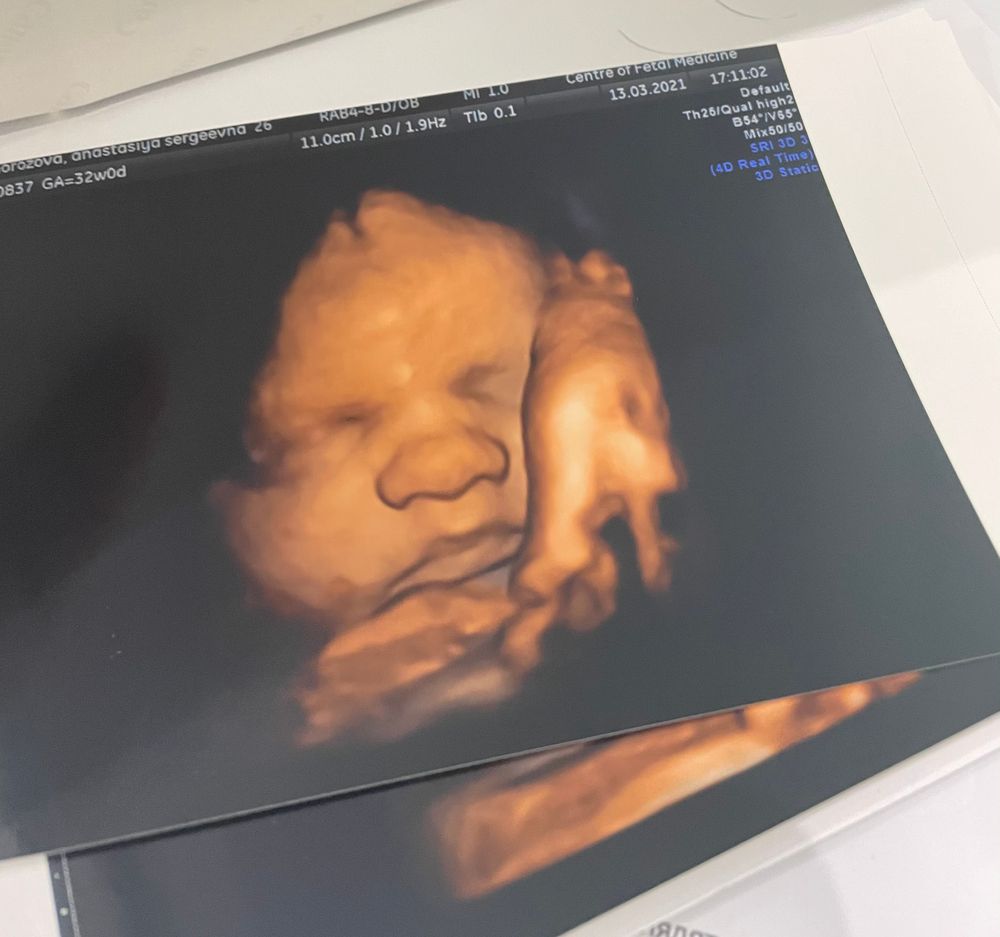

3 скрининг ✔️ 32 недели

Но! Этот Человек покорил моё сердце, а особенно то, что он улыбался 😍

Копия мужа и его младшего братика, от меня возможно только щеки 😅 а ещё мы крупненькие, сейчас весим 2150, на выходе подсчитали где-то 3800 и рост 54см 🙈 роды будут веселыми 👌🏻 Лежит правильно, обвития нет, зато есть трудовая мозоль на губе потому что кто-то активно сосет пальцы в животике 😊 а ещё сказали что родимся с шевелюрой, так как она уже огого какая 😅